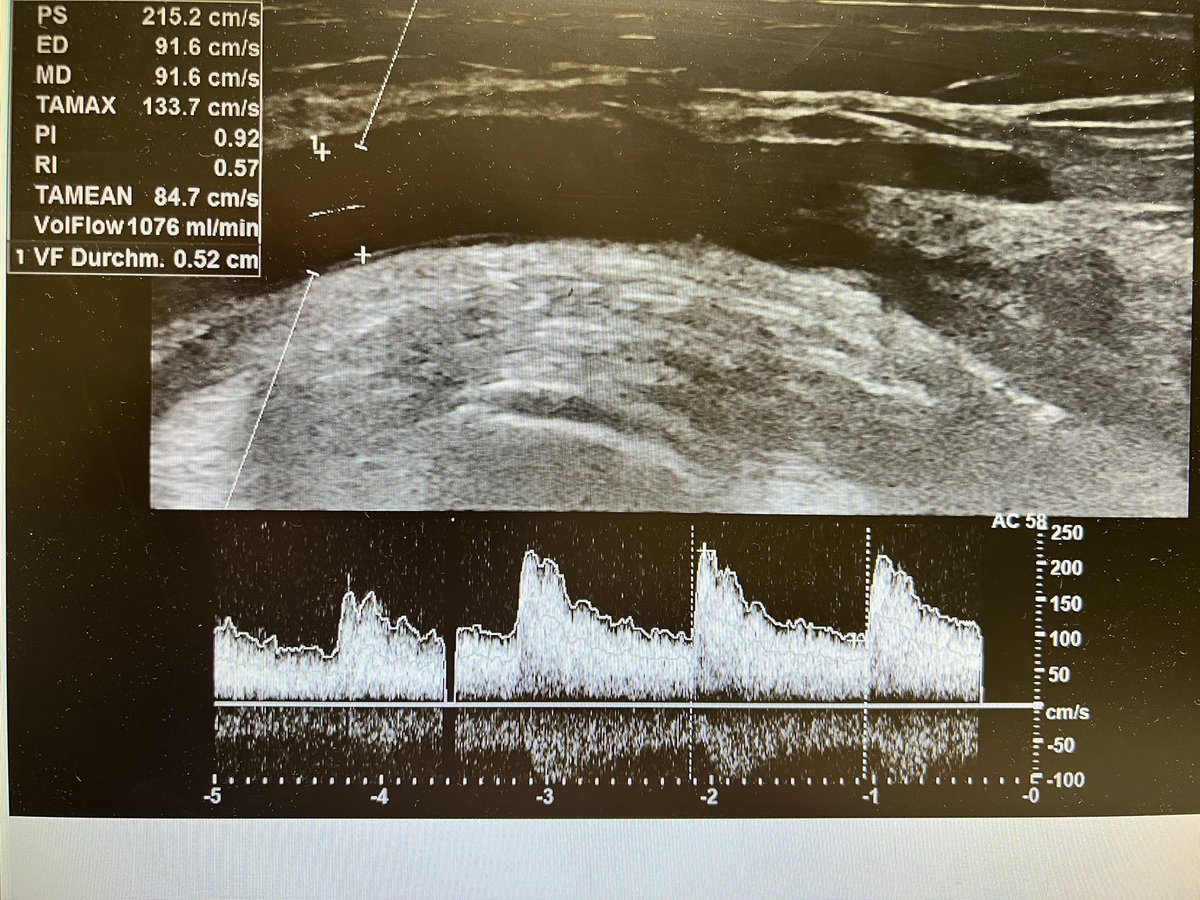

Brachial artery and mid level forearm cephalic vein before (fig 1-2) and exactly 2 days!!!! after (fig 3-4) the creation of a

#VasQ#RCAVF in a#CKD patient@wasse_m@jimbog_76@OBaumgaertner_#VascularAccessCenter#Hamburg#Barmbek#LaminateMedicalpic.twitter.com/0aX0710Wnu